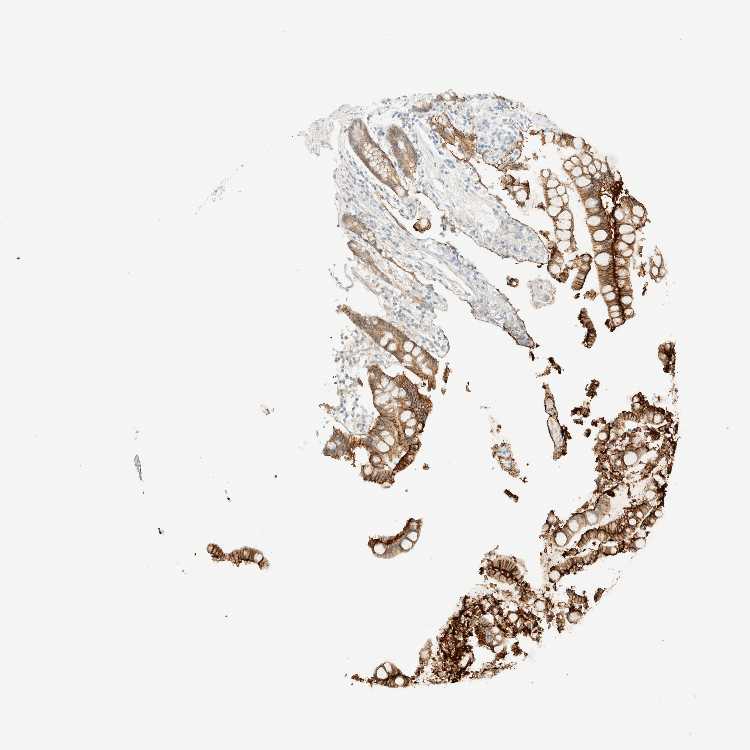

COLON - Antibody stainingi

Antibody staining in the annotated cell types in the current human tissue is reported as not detected, low, medium, or high, based on conventional immunohistochemistry profiling in selected tissues. This score is based on the combination of the staining intensity and fraction of stained cells.

Each image is clickable and will lead to virtual microscopy that enables deeper exploration of all samples and also displays staining intensity scores, fraction scores and subcellular localization as well as patient and tissue information for each sample.

Antibody HPA018858Antibody CAB025943

Endocrine cells High-

Endothelial cells Not detectedNot detected

Enterocytes High-

Enterocytes - Microvilli Not detected-

Fibroblasts Not detected-

Glandular cells -High

Goblet cells High-

Mucosal lymphoid cells Not detected-

Peripheral nerve/ganglion -Not detected